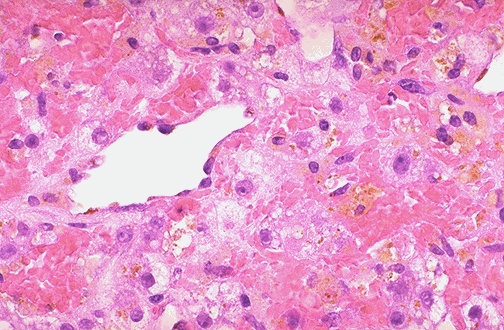

| If the passive congestion is pronounced, then there can be centrilobular necrosis, because the oxygenation in zone 3 of the hepatic lobule is not great. The light brown pigment seen here in the necrotic hepatocytes around the central vein is lipochrome. |